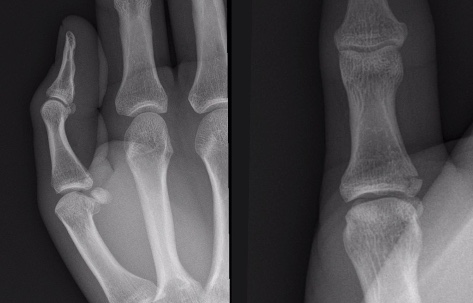

Fracture de MCP 1 (Pouce du skieur/Gamekeeper’s thumb)

- ne PAS fait de stress view pour mieux voir = risque de blessure chirurgicale

Fracture de MC 1

- mnemotechnique: Benett = Bi